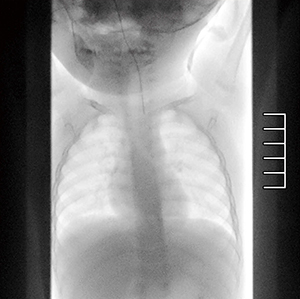

症例2 乳児上部消化管造影時の栄養カテーテル挿入

線量モードはNormalであるが,輝度不足であったためデジタル輝度+2とした。線量を上げることなくデジタル輝度調整のみにて栄養カテーテルおよび縦隔の視認性を確保した。